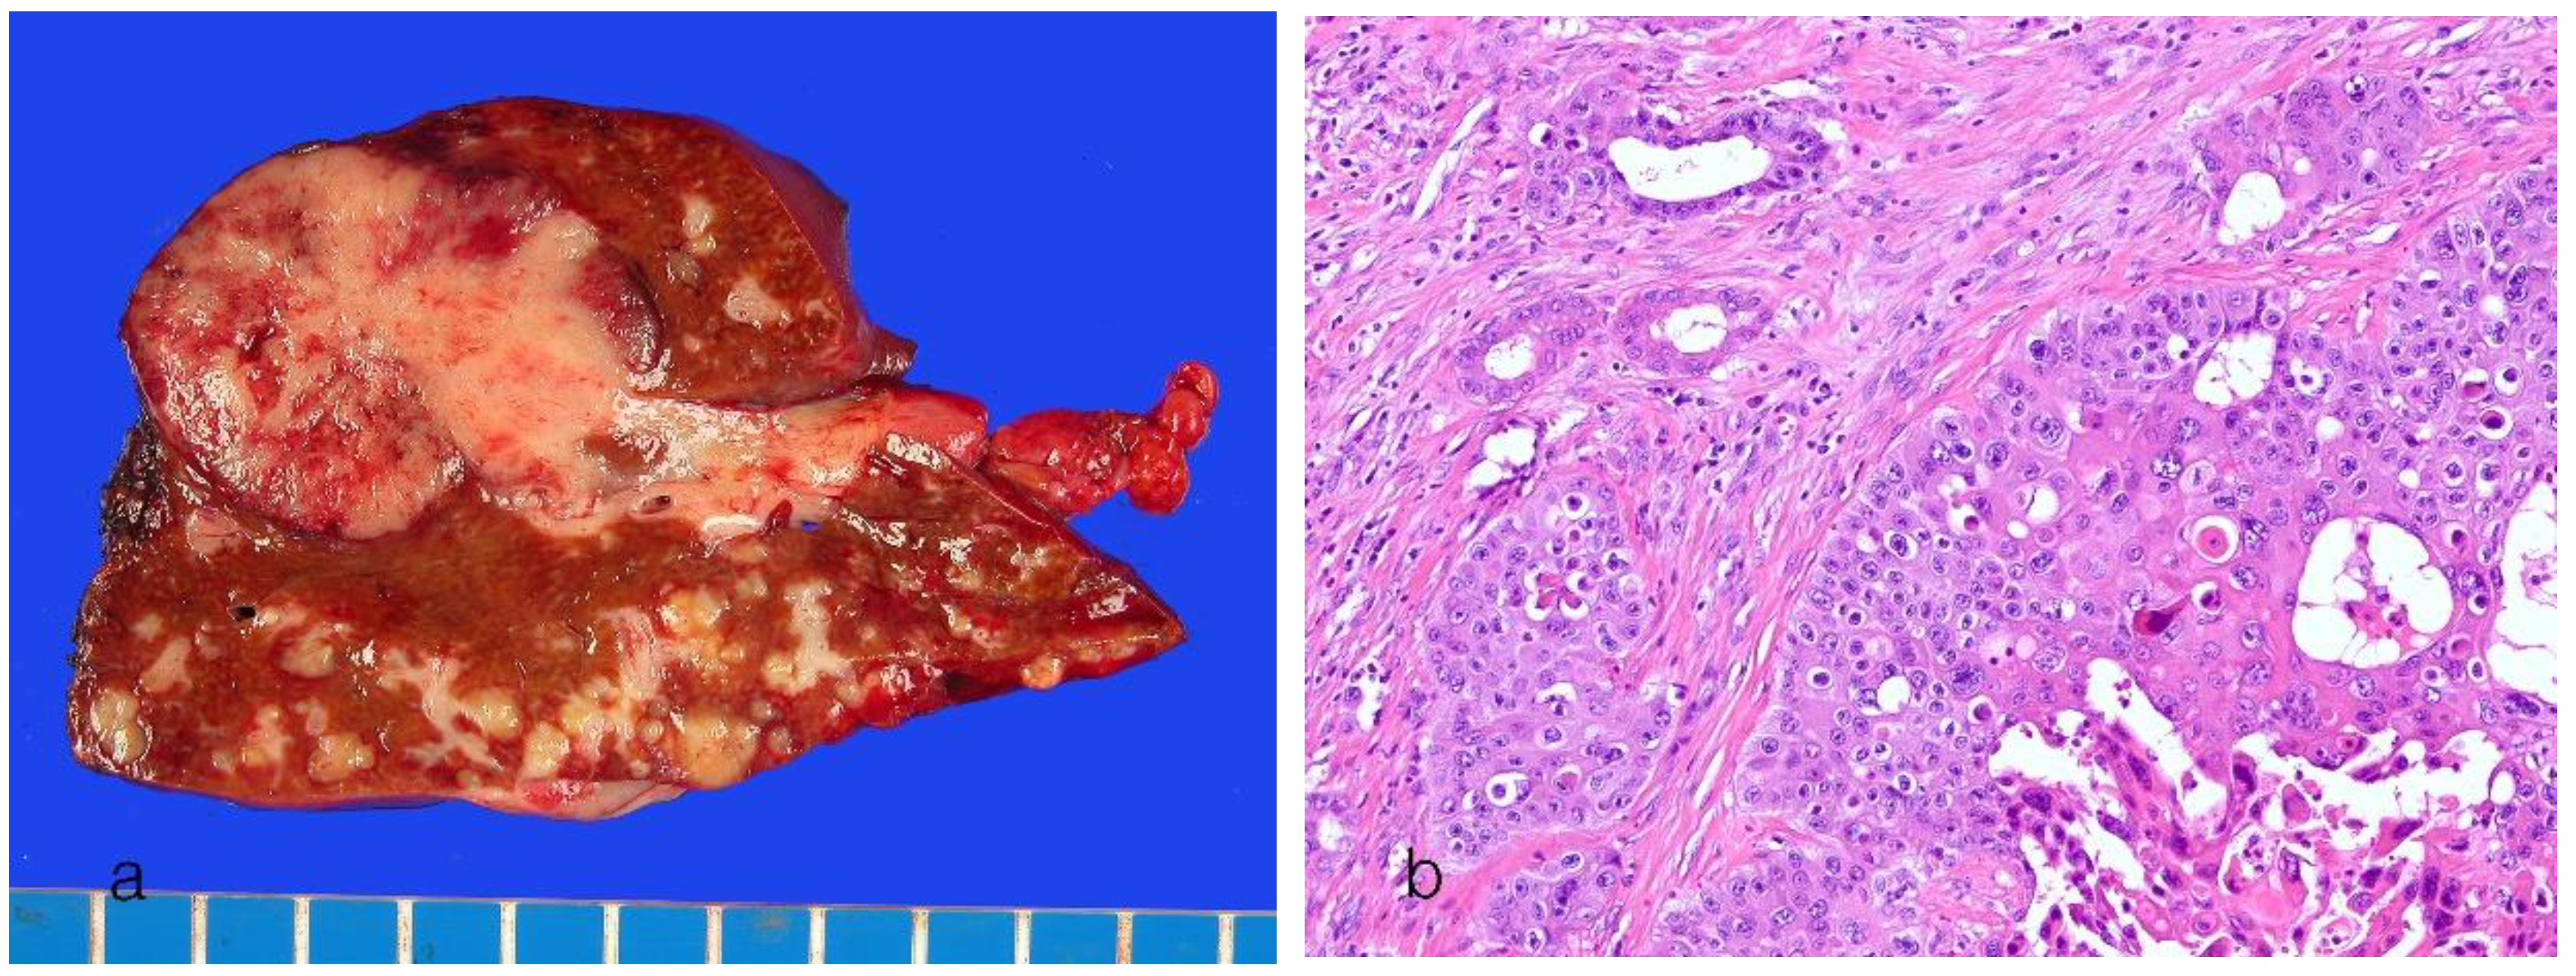

| Goss features | MF pattern | PI pattern, PI + MF pattern |

| Origins of cells | Small bile ducts and bile ductules, hepatic progenitor cells? | Intrahepatic large bile ducts, peribiliary glands |

| Histology | Small ductal components: tubular pattern with low columnar to cuboidal cells and desmoplastic reaction Ductular components, cuboidal epithelia showing ductular or cord-like pattern with slit-like lumen and desmoplastic reaction |

Ductal or tubular pattern with columnar to cuboidal epithelium, with desmoplastic reaction |